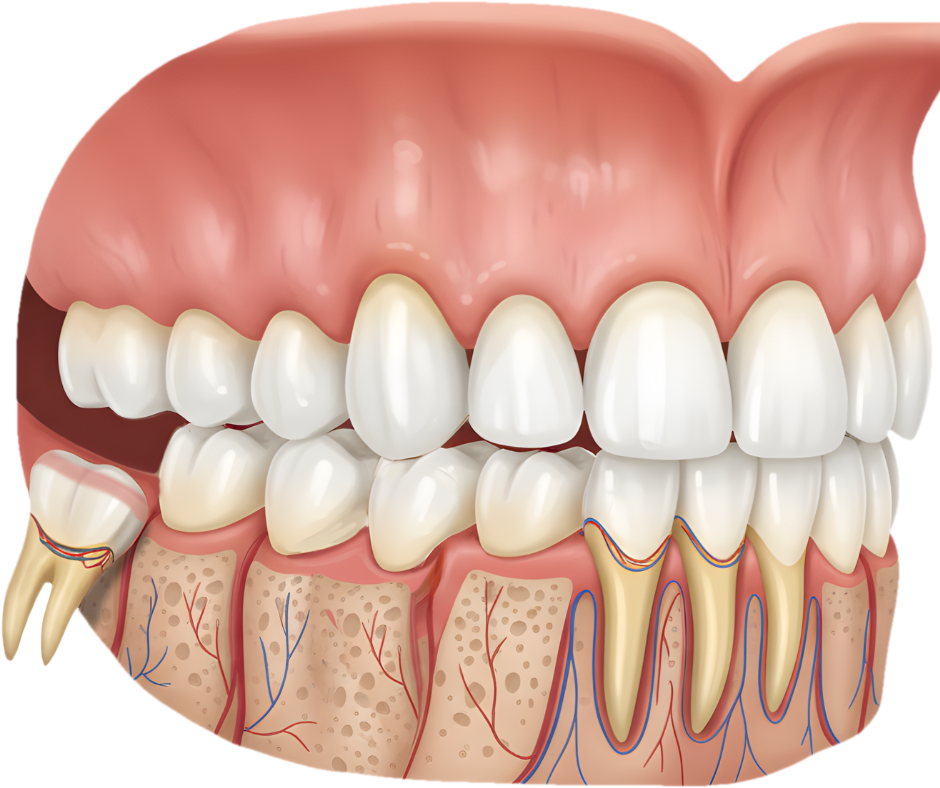

Wisdom teeth are the last set of molars to erupt—usually between the ages of 17 and 25. While some wisdom teeth grow without issues, many do not have enough space to erupt properly. This can lead to pain, swelling, infection, crowding, and damage to nearby teeth.

- Impacted (partially or fully trapped) wisdom teeth

- Tooth decay or damage to adjacent teeth